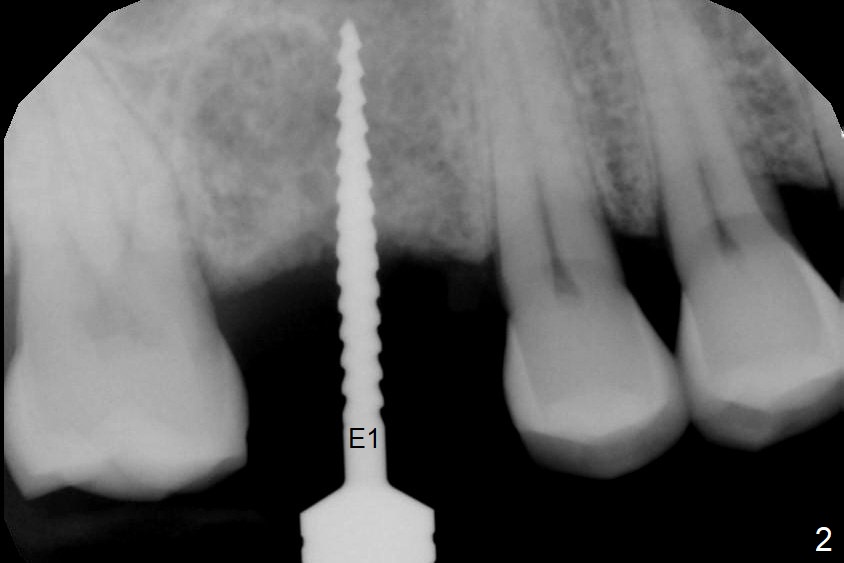

A 54-year-old man has lost the tooth #3 for 6 months with complicated sinus floor morphology (Fig.1 red dashed line (one of 2 outlines), bone height ~ 7 mm). Initial osteotomy depth is ~ 6 mm (Fig.2,3 with 1.2 mm initial drill and DIO Bone Expander 1 (E1 with diameter 1.0/1.6 mm). Following change in the trajectory, E2 (1.3/2.3 mm) is used for ~ 8 mm (Fig.4). After application of E4 (2.4/3.7 mm, Fig.5) and E5 (3.0/4.4 mm) for ~ 12 mm, the sinus membrane is found to have perforated. With placement of collagen membrane and cortical allograft (Fig.6 *), a 5x8.5 mm Hiossen implant is placed with >50 Ncm.